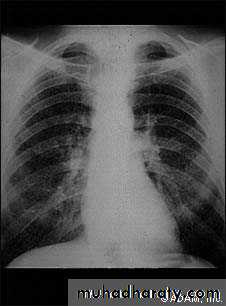

Pulmonary fibrosis caused by prolonged inhalation of coal dust. Which divided into;1-Simple coal worker's pneumoconiosis (SCWP); scattered discrete fibrotic lesions, does not cause pulmonary function abnormalities or progress following cessation of exposure.

2-Complicated pneumoconiosis; large dense masses appear mainly in the upper lobes (also known as progressive massive fibrosis, PMF). Presented as cough, production of sputum, that may be black (melanoptysis) and breathlessness. Respiratory failure after cessation of exposure and right ventricular failure.

The clinical and radiological features are similar to those of coal worker's pneumoconiosis, with multiple well circumscribed 3–5-mm nodular opacities, predominantly in the mid- and upper zones

Enlargment of the hilar glands with an 'egg-shell' pattern of calcification is characterestic.